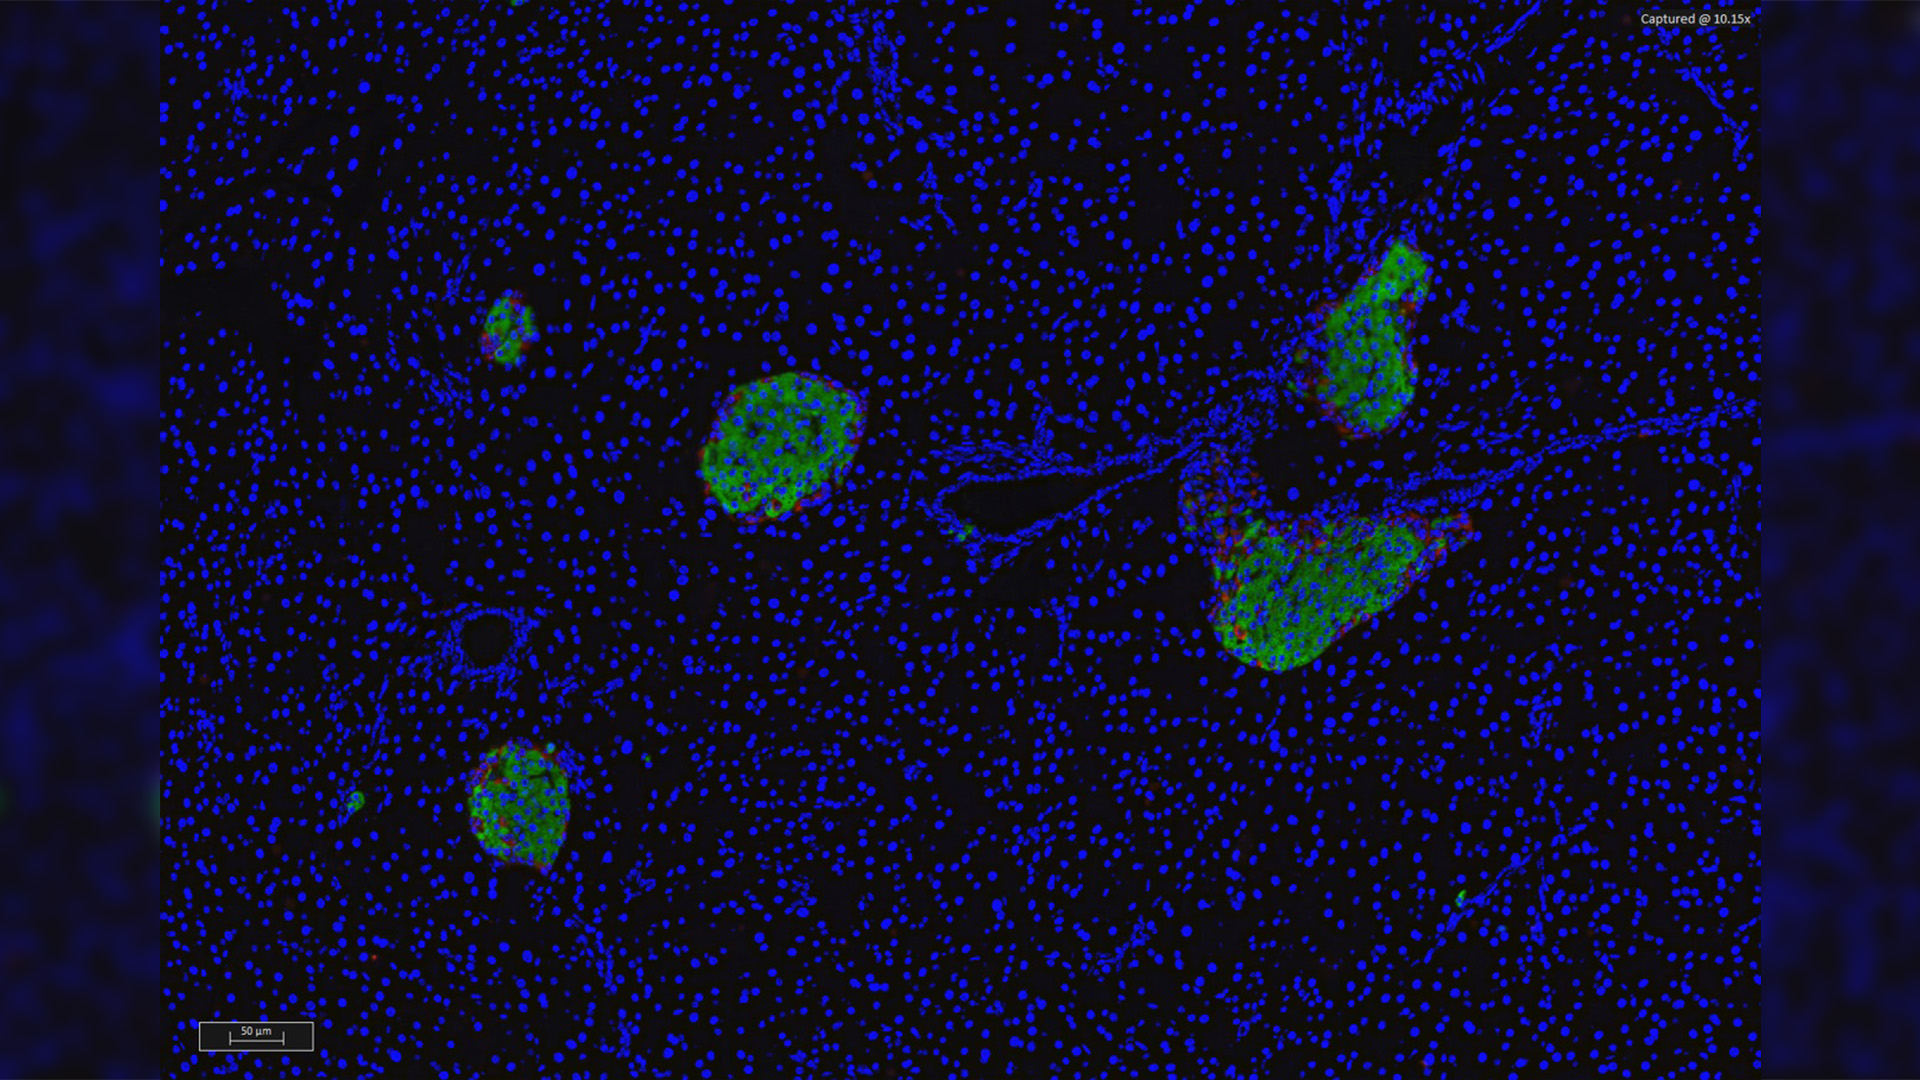

© Christophe Magnan

L’équipe de recherche Reglys, dirigée par le Pr C. Magnan, vient de mettre en évidence le rôle du bulbe olfactif dans le processus de sécrétion d’insuline par le pancréas.

Lorsque l’on mange, le système gastro-intestinal sécrète une hormone appelée glucagon like peptide-1 (GLP-1). Le GLP-1 circulant dans le sang stimule à son tour la sécrétion d’insuline par le pancréas de façon à assimiler les divers sucres ingérés. Mais le GLP-1, utilisée par ailleurs comme antidiabétique, est également produit localement dans le cerveau au niveau du bulbe olfactif, lorsque ce dernier détecte une odeur. Les chercheurs de l’équipe Reglys ont mis en évidence le circuit par lequel le GLP-1, sécrétée par le bulbe olfactif, influence l’activité du pancréas et stimule la sécrétion d’insuline. Les résultats des travaux montrent que le GLP-1 sécrété par le bulbe olfactif ne passe pas dans la circulation sanguine mais agit à courte distance pour contrôler l’hypothalamus non loin de là. Lorsque le signal envoyé par le GLP-1 est détecté, L’hypothalamus entre alors en action en envoyant des signaux nerveux au pancréas, via le système nerveux sympathique, qui déclenchent alors la sécrétion d’insuline.

Le GLP-1 produit dans le bulbe olfactif envoie un signal vers l’hypothalamus. L’hypothalamus contrôle l’activité nerveuse sympathique qui contrôle à son tour la sécrétion d’insuline. Lorsque les neurones du GLP-1 s’activent pendant un repas la sécrétion d’insuline est stimulée via ce réseau neuronal.